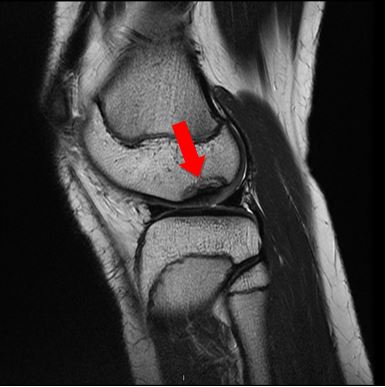

Vid osteokondrit lossnar det broskaktiga benfragmentet från sin fäste. Orsaken till problemet är okänd. Sjukdomen är vanligare hos pojkar än hos flickor. Symtomen kan förbättras av sig själva när barnet växer, men i vissa fall kan man överväga ingrepp.

Diagnosen och valet av behandlingsform grundar sig på läkarens undersökning av knät och på bilddiagnostiska undersökningar (röntgenundersökning och/eller magnetundersökning), som bedöms från fall till fall.